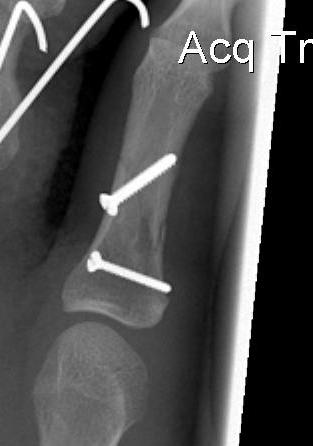

B. Long oblique / spiral fractures

Definition

- fracture must be at lease 2 x diameter bone

- can treat with 2 x lag screws

- one perpedicular to fracture to lag

- one perpendicular to shaft to resist shear

Options

- percutaneous K wires / screw fixation / plating